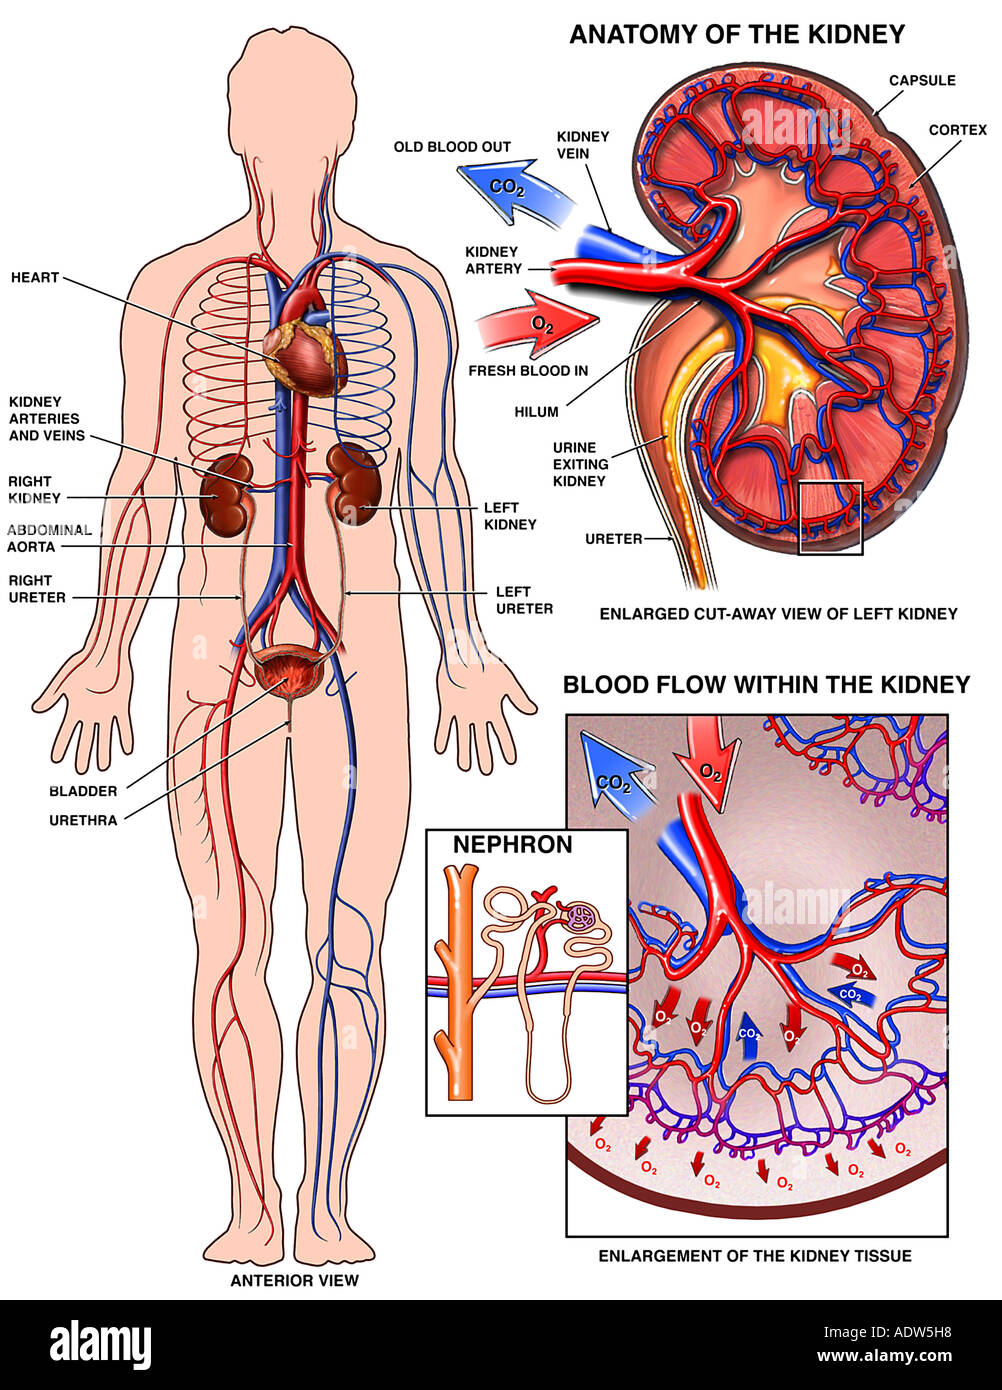

The kidneys alone perform the functions just described and manufacture urine in the process while the other organs of the urinary system provide temporary storage reservoirs for urine or serve as transportation channels to carry it from one body region to another. The article anatomy and physiology of the kidney is the basis for this aorn journal independent study.

The kidneys are 11 centimeters long paired reddish brown organs situated on the posterior wall of the abdominal cavity one on each side of the vertebral column and capped by the adrenal gland. H ions are produced as a natural byproduct of the metabolism of dietary proteins and accumulate in the blood over time. Connective tissue anchors the kidneys to surrounding structures and helps maintain their normal position.

Upper portions of the kidneys are somewhat protected by the eleventh and twelfth ribs figure 1. Anatomy of the kidneys. Each kidney weighs about 125175 g in males and 115155 g in females.

Due to the presence of the liver the right kidney is slightly lower than the left kidney. They are about 1114 cm in length 6 cm wide and 4 cm thick and are directly covered by a fibrous capsule composed of dense. Anatomy of the urinary system.

The kidneys monitor and regulate the levels of hydrogen ions h and bicarbonate ions in the blood to control blood ph. Glomerular filtration glomerular filtration is the renal process whereby fluid in the blood is filtered across the capillaries of the glomerulus. The right kidney is lower than the left due to displacement by the liver.

Location of the kidneys there are two kidneys which lie retroperioneally in the lumbar area. The angiotensinconverting enzyme converts angiotensin i to angiotensin ii which stimulates the adrenal cortex to secrete aldosterone a hormone that is involved in increasing blood pressure. The basic anatomy and physiology of the kidney how kidney function changes through life the anatomy of the kidney the kidneys are comple x and beautiful organs.